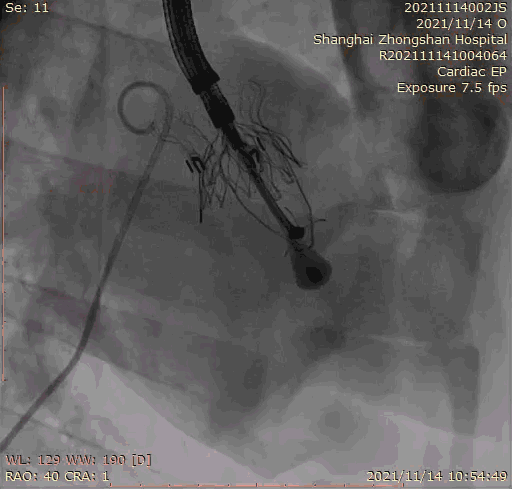

本次臨床前研究經(jīng)右側(cè)頸靜脈置入LuX-Valve Plus輸送系統(tǒng)可調(diào)彎鞘管,在DSA及超聲引導(dǎo)下將人工三尖瓣瓣膜植入到原有三尖瓣位置,利用獨(dú)特的錨定技術(shù)將人工瓣膜支架可靠固定在預(yù)定的位置。

Lux-Valve是全球第一款具有我國(guó)完全自主知識(shí)產(chǎn)權(quán)的經(jīng)導(dǎo)管介入三尖瓣置換系統(tǒng),利用前瓣夾持及室間隔錨定的復(fù)合方式進(jìn)行瓣膜裝置的固定,不依賴(lài)瓣環(huán)徑向支撐力,同時(shí)采用自適應(yīng)復(fù)合裙邊材料,有效的貼合密封柔軟的三尖瓣瓣環(huán),針對(duì)于三尖瓣返流的患者有優(yōu)異的療效。Lux-Valve Plus采用全新的經(jīng)血管輸送系統(tǒng),經(jīng)頸靜脈入路創(chuàng)傷更小,可以進(jìn)一步降低手術(shù)風(fēng)險(xiǎn)。相信在后期正式臨床研究開(kāi)展中,Lux-Valve Plus必定會(huì)為更多的三尖瓣反流患者帶來(lái)福音。